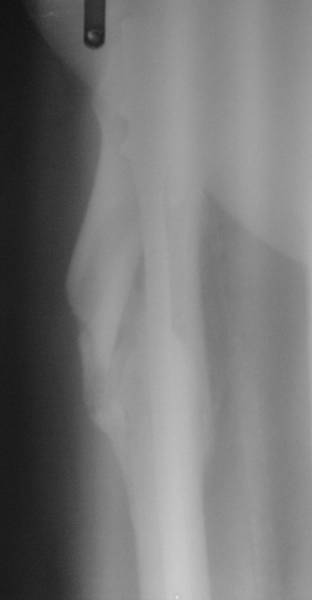

Нашел в архиве наш проблемный остесинтез  на таком-же штифте с  варусным

смещением проксимального отломка, который ,правда, успешно

консолидировался в срок.